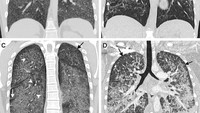

Spektrum cedera paru-paru yang terkait dengan nodul centrilobular (CNs) dalam rokok elektrik atau cedera paru terkait penggunaan produk vaping (Foto: American College of Chest Physicians).